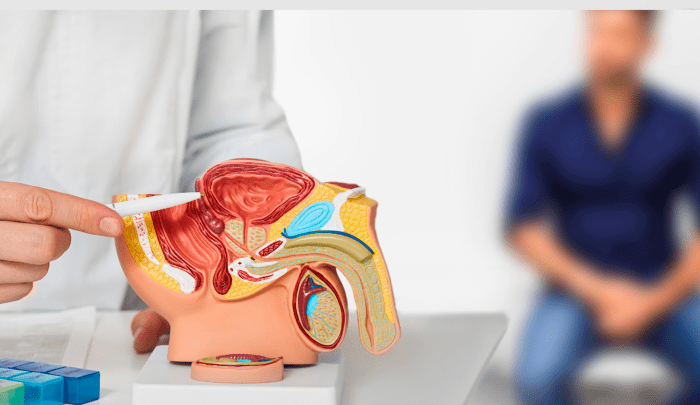

¿Miedo al tacto rectal? ¡Hay alternativas para la detección oportuna del cáncer de próstata!

1 de cada 8 hombres será diagnosticado con cáncer de próstata durante su vida.Aproximadamente el 80% de los hombres con cáncer de próstata en etapa inicial no experimentan síntomas notorios. Recientemente el cáncer de próstata se convirtió en el cáncer más frecuente entre los hombres de todo el mundo. Ya superó al de pulmón, colon … Continuar leyendo ¿Miedo al tacto rectal? ¡Hay alternativas para la detección oportuna del cáncer de próstata!

¿Cuáles son los síntomas del cáncer de próstata?

La próstata es un órgano glandular que forma parte del aparato reproductor masculino. Su función principal es producir el líquido del semen a lo largo de la vida de la persona. Ante la exposición de la testosterona, a los 50 años o 60 años de edad la próstata empieza tener un crecimiento natural, conocido como hiperplasia. Sin embargo, cuando … Continuar leyendo ¿Cuáles son los síntomas del cáncer de próstata?